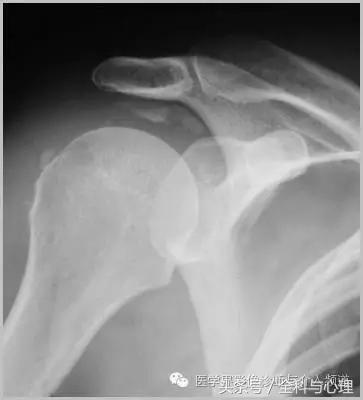

六、肌腱钙化/滑囊炎并钙化

肩关节最常见:肱二头肌长头、肩峰下滑囊钙化,可伴有急性疼痛、肿胀,局部压痛。

肱二头肌肌腱钙化(肩周炎)

肩周炎